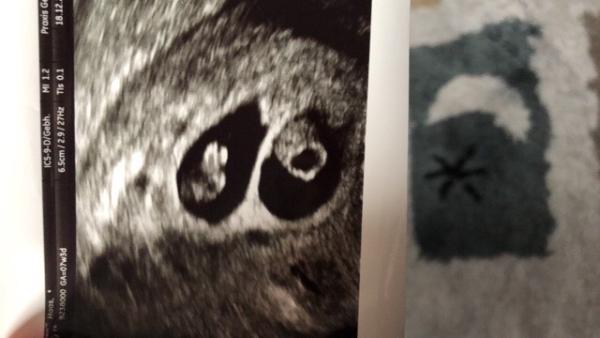

Hier meine Babys in der 8. SSW

Bild zu